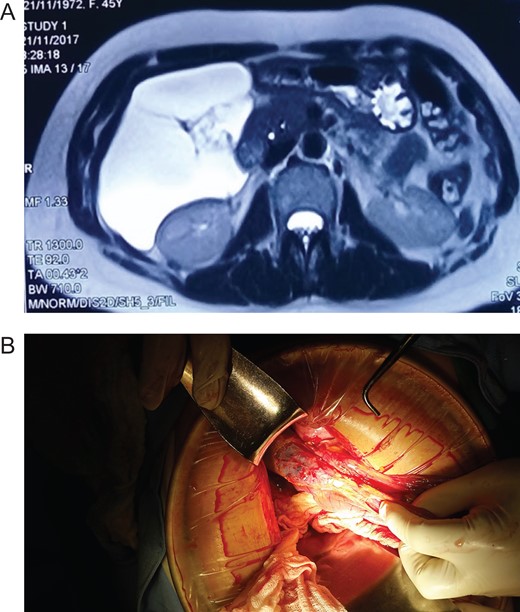

Patient is a 45-year-old female patient, with past medical history of gastritis. Six months before she sought medical attention, she was complaining of mild upper abdominal pain, however, due to her previous condition she was medicated with proton pump inhibitors assuming that the pain was due to her gastritis. In the last 3 months, she noticed a mass in her upper abdomen and the pain became more severe and started to affect her daily activities, thus she presented to a routine physical exam. No weight loss or other constitutional symptoms were noticed. Also no history of malignancy in her family was mentioned. On clinical examination, a 12 × 15 cm2 mass was discovered on her upper abdomen, mild pain was found on palpation but no tenderness was present. An abdominal ultrasonography revealed a 15 × 15 cm2 septate thin-walled giant cystic mass, it was anechoic and had a volume of ~735 ml. The cyst occupied most of the hepatorenal space and it was in intimate contact with the liver, right kidney and pancreas (Fig. 1A). Due to the size of the mass, CT was requested, it revealed well-defined 19.7 × 15 × 10 cm3 giant cyst, the cyst was located within the small bowel mesentery and it was in intimate contact with the liver, gallbladder, pancreas and right kidney (Fig. 2A). Nevertheless, the tomography could not rule out that the mass had some sort of communication with the bile duct or the pancreas. This is why a magnetic resonance cholangiopancreatography found that the cyst was attached but had no communication with the bile duct or the pancreas (Fig. 3A). CBC and blood work was normal.

(A) CT revealing a well-defined 19.7 × 15 × 10 cm3 giant cyst. (B) Giant cyst surrounded by the bowel. (C) Pathology, cyst wall covered by adipose tissue. (Hematoxylin and eosin staining 40×.)

Due to the size of the cyst and clinical condition surgery was planned. At laparotomy, a 19 × 15 × 10 cm3 mesenteric cyst was discovered (Fig. 1B), the cyst was near the root of the small bowel mesentery but did not compromise its main vessels, it had a yellowish appearance (Fig. 2B), and clear fluid was found within the cyst. Multiple adhesion were identified between the cyst wall and the transverse colon, liver, third portion of the duodenum and gallbladder. With these findings surgery was straightforward, complete resection of the cystic mass was performed, however, the cyst wall was completely attached to the body of the gallbladder and could not be resected without compromising it (Fig. 3B), so a cholecystectomy was performed as well. After this, the remainder of the procedure continued without any complication.